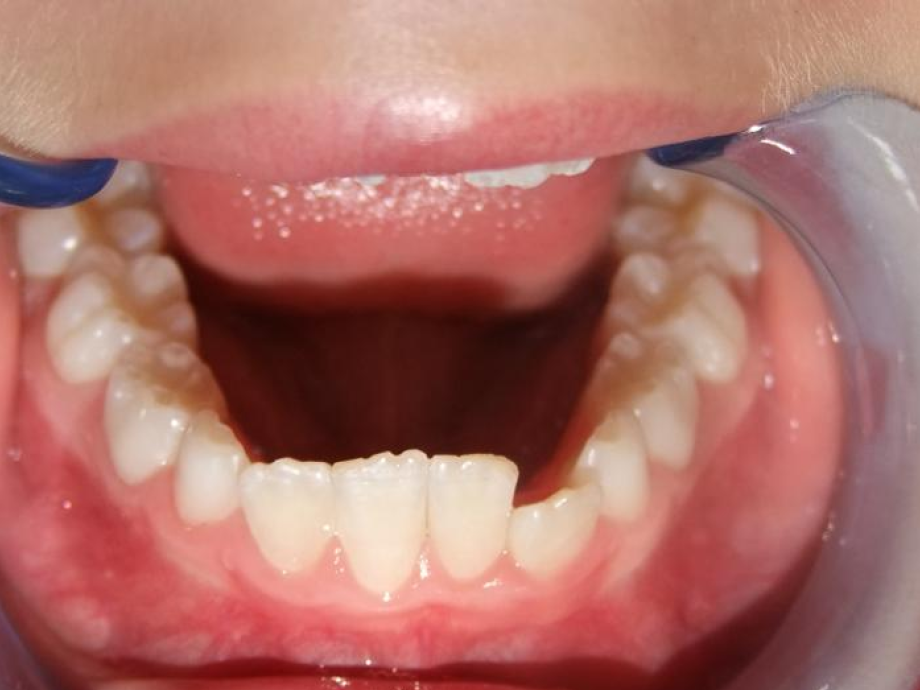

eindfoto

Leeftijd bij aanvang: 9 jaar

1-6 Bonded Hyrax + volledig vast onderkaak + TransForce onderkaak

7-13 Twin Block

14-28 volledig vast onder- en bovenkaak + rotator

Retentie: Wrap-Around

Leeftijd bij retentie: 12 jaar